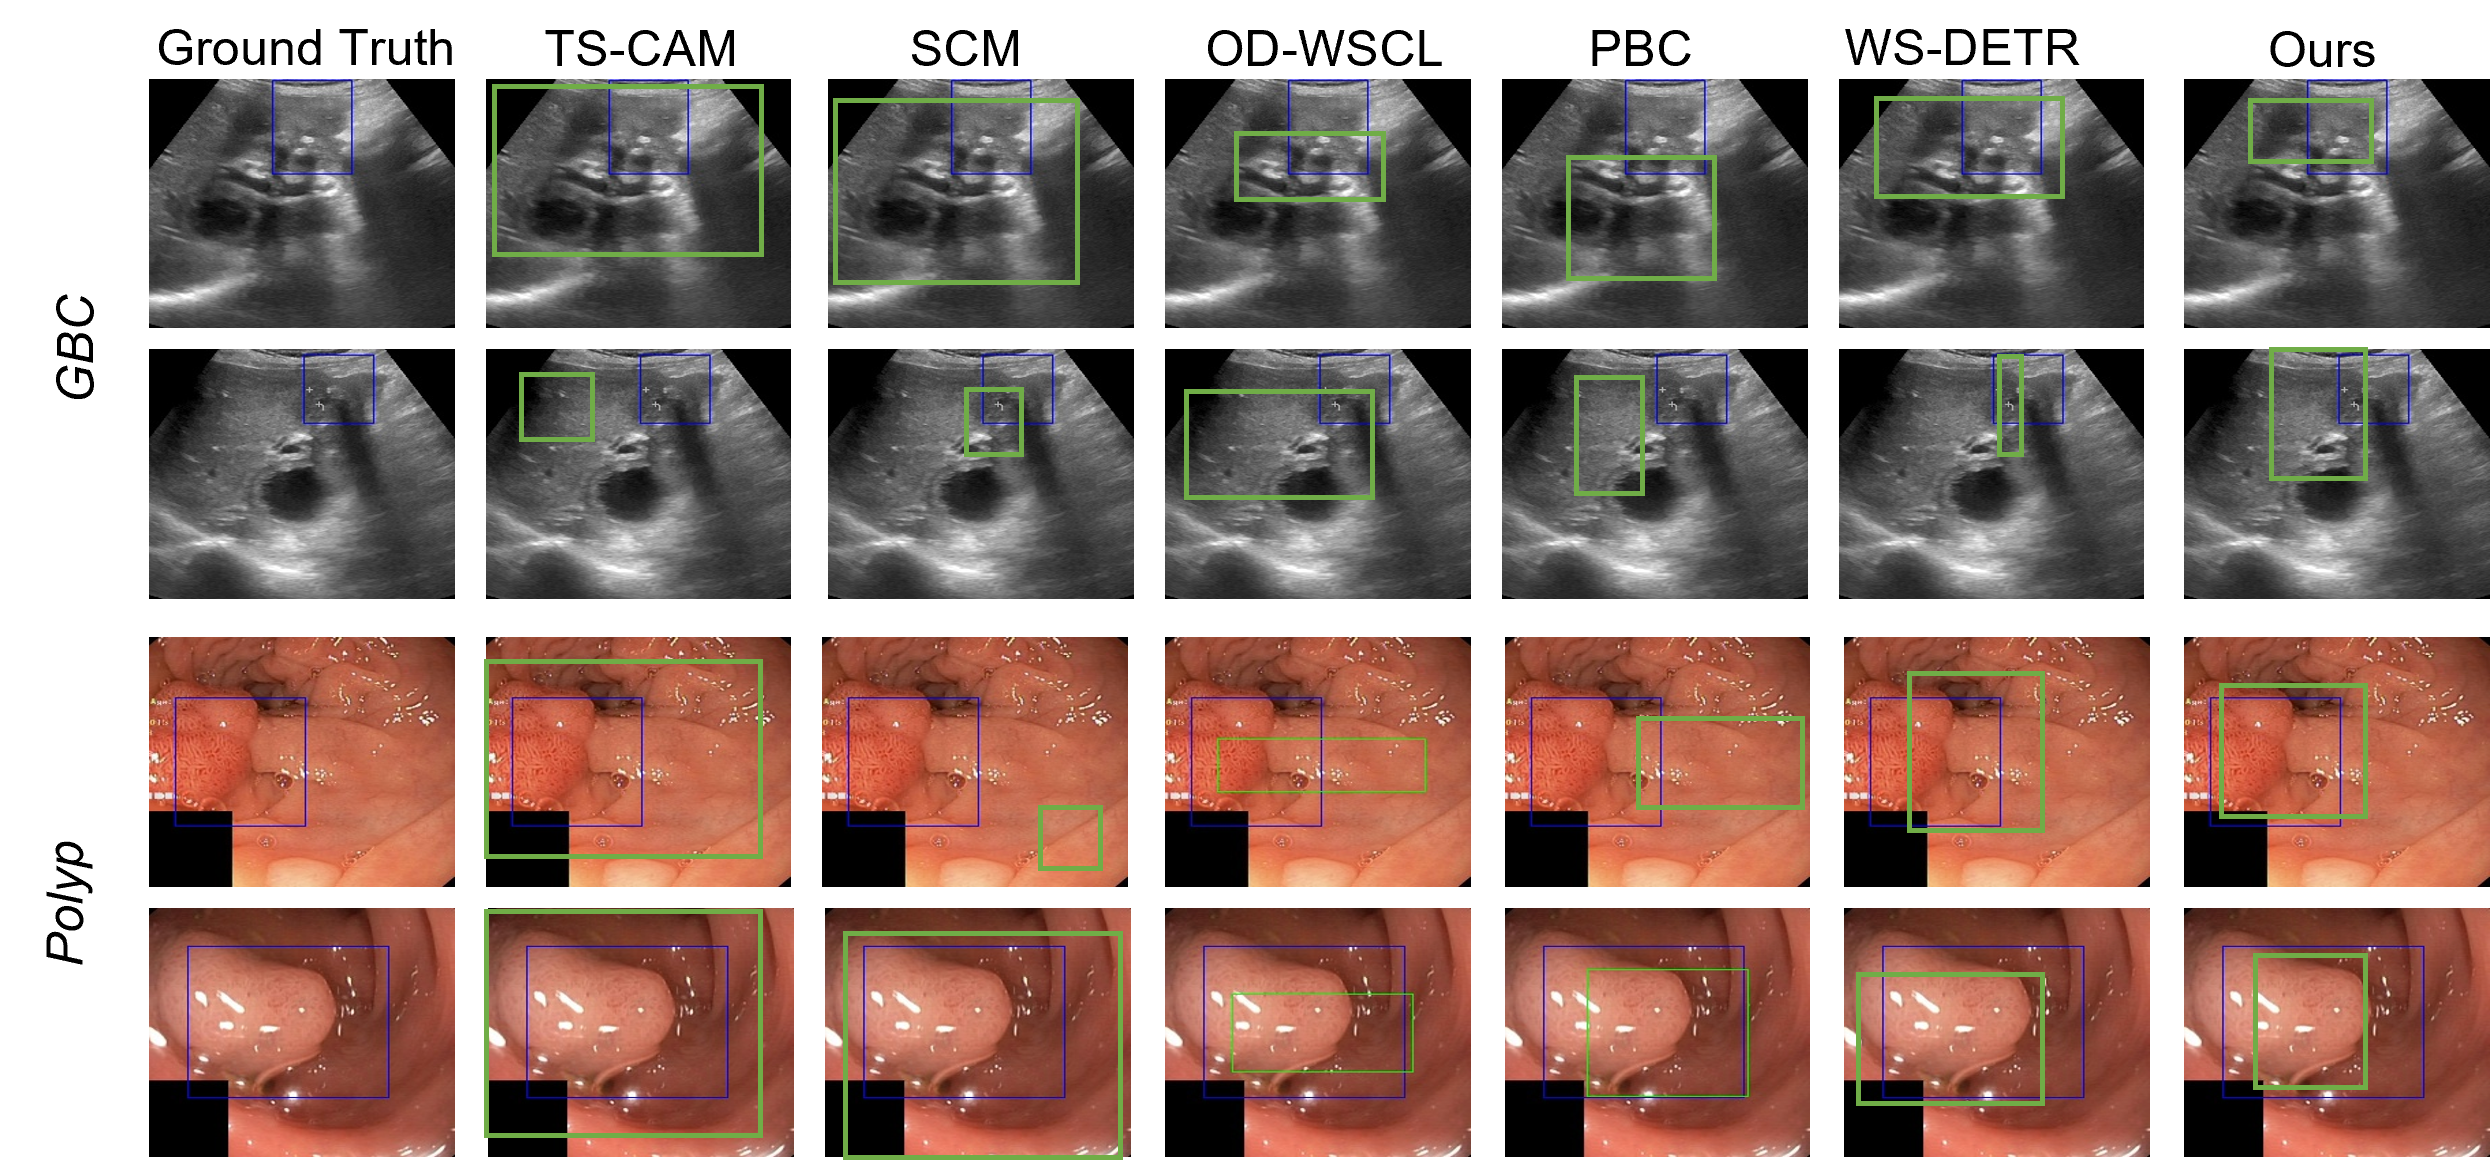

Refer to caption

Figure 4: Qualitative analysis of the predicted bounding boxes. Ground truths are in blue, and predictions are in green. We compare with SOTA WSOD techniques and our proposed method. Our method predicts much tighter bounding boxes that cover the clinically significant disease regions.

Comparison with SOTA: Tab. 1 shows the bounding box localization results of the WSOD task. Our method surpasses all latest SOTA WSOD techniques by 9 points, and establishes itself as a strong WSOD baseline for GBC localization in US images. Our method also achieves 7-point higher AP score for polyp detection. We present visualizations of the predicted bounding boxes in Fig. 4 which shows that the localization by our method is more precise and clinically relevant as compared to the baselines.